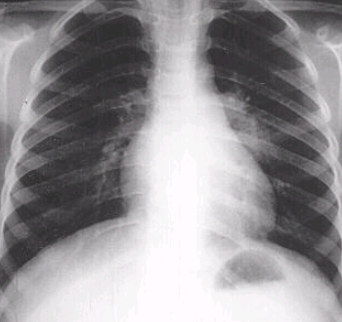

잠복결핵감염은 결핵간염검사에서 양성으로 판정되고 흉부 X선 검사 등 결핵검사를 실시하여 활동성 결핵이 제외된 경우 잠복결핵감염으로 진단합니다.

결핵은 증상 여부나 진찰, 흉부 X선 검사, 객담 결핵균 검사 등을 통해서도 확인합니다.